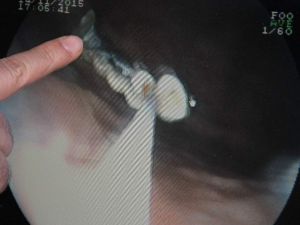

Kaybettiği 5 Dişi Bağırsaklarından Çıktı